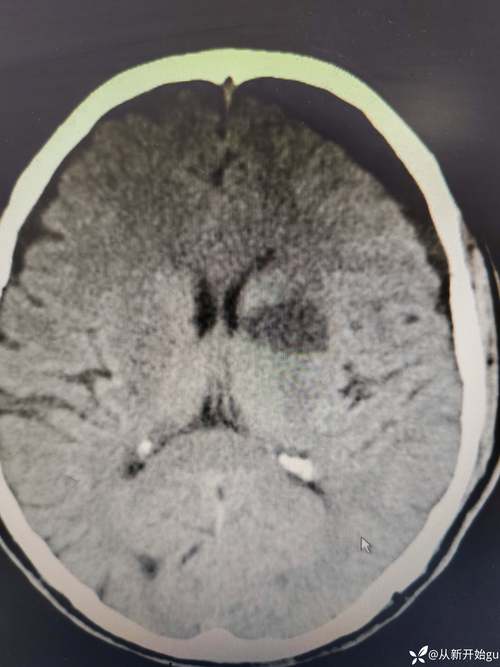

- 什么是“脑沟裂消失”? 这是指在医学影像(主要是CT或MRI)上,原本清晰可见的脑沟和脑回的形态变得模糊、平坦,甚至看不到了。

第三步:脑沟裂消失

大脑半球的整体肿胀,就像一个吹得过大的气球,其表面的褶皱(脑沟裂)被撑开、拉平,最终在CT或MRI上表现为“脑沟裂消失”。

- 中线移位: 大脑半球严重肿胀时,会将脑组织从一侧推向另一侧,压迫对侧的大脑,并使位于大脑中间的结构(如脑室)偏移,这在影像上称为“中线结构移位”,这是颅内高压的严重表现。